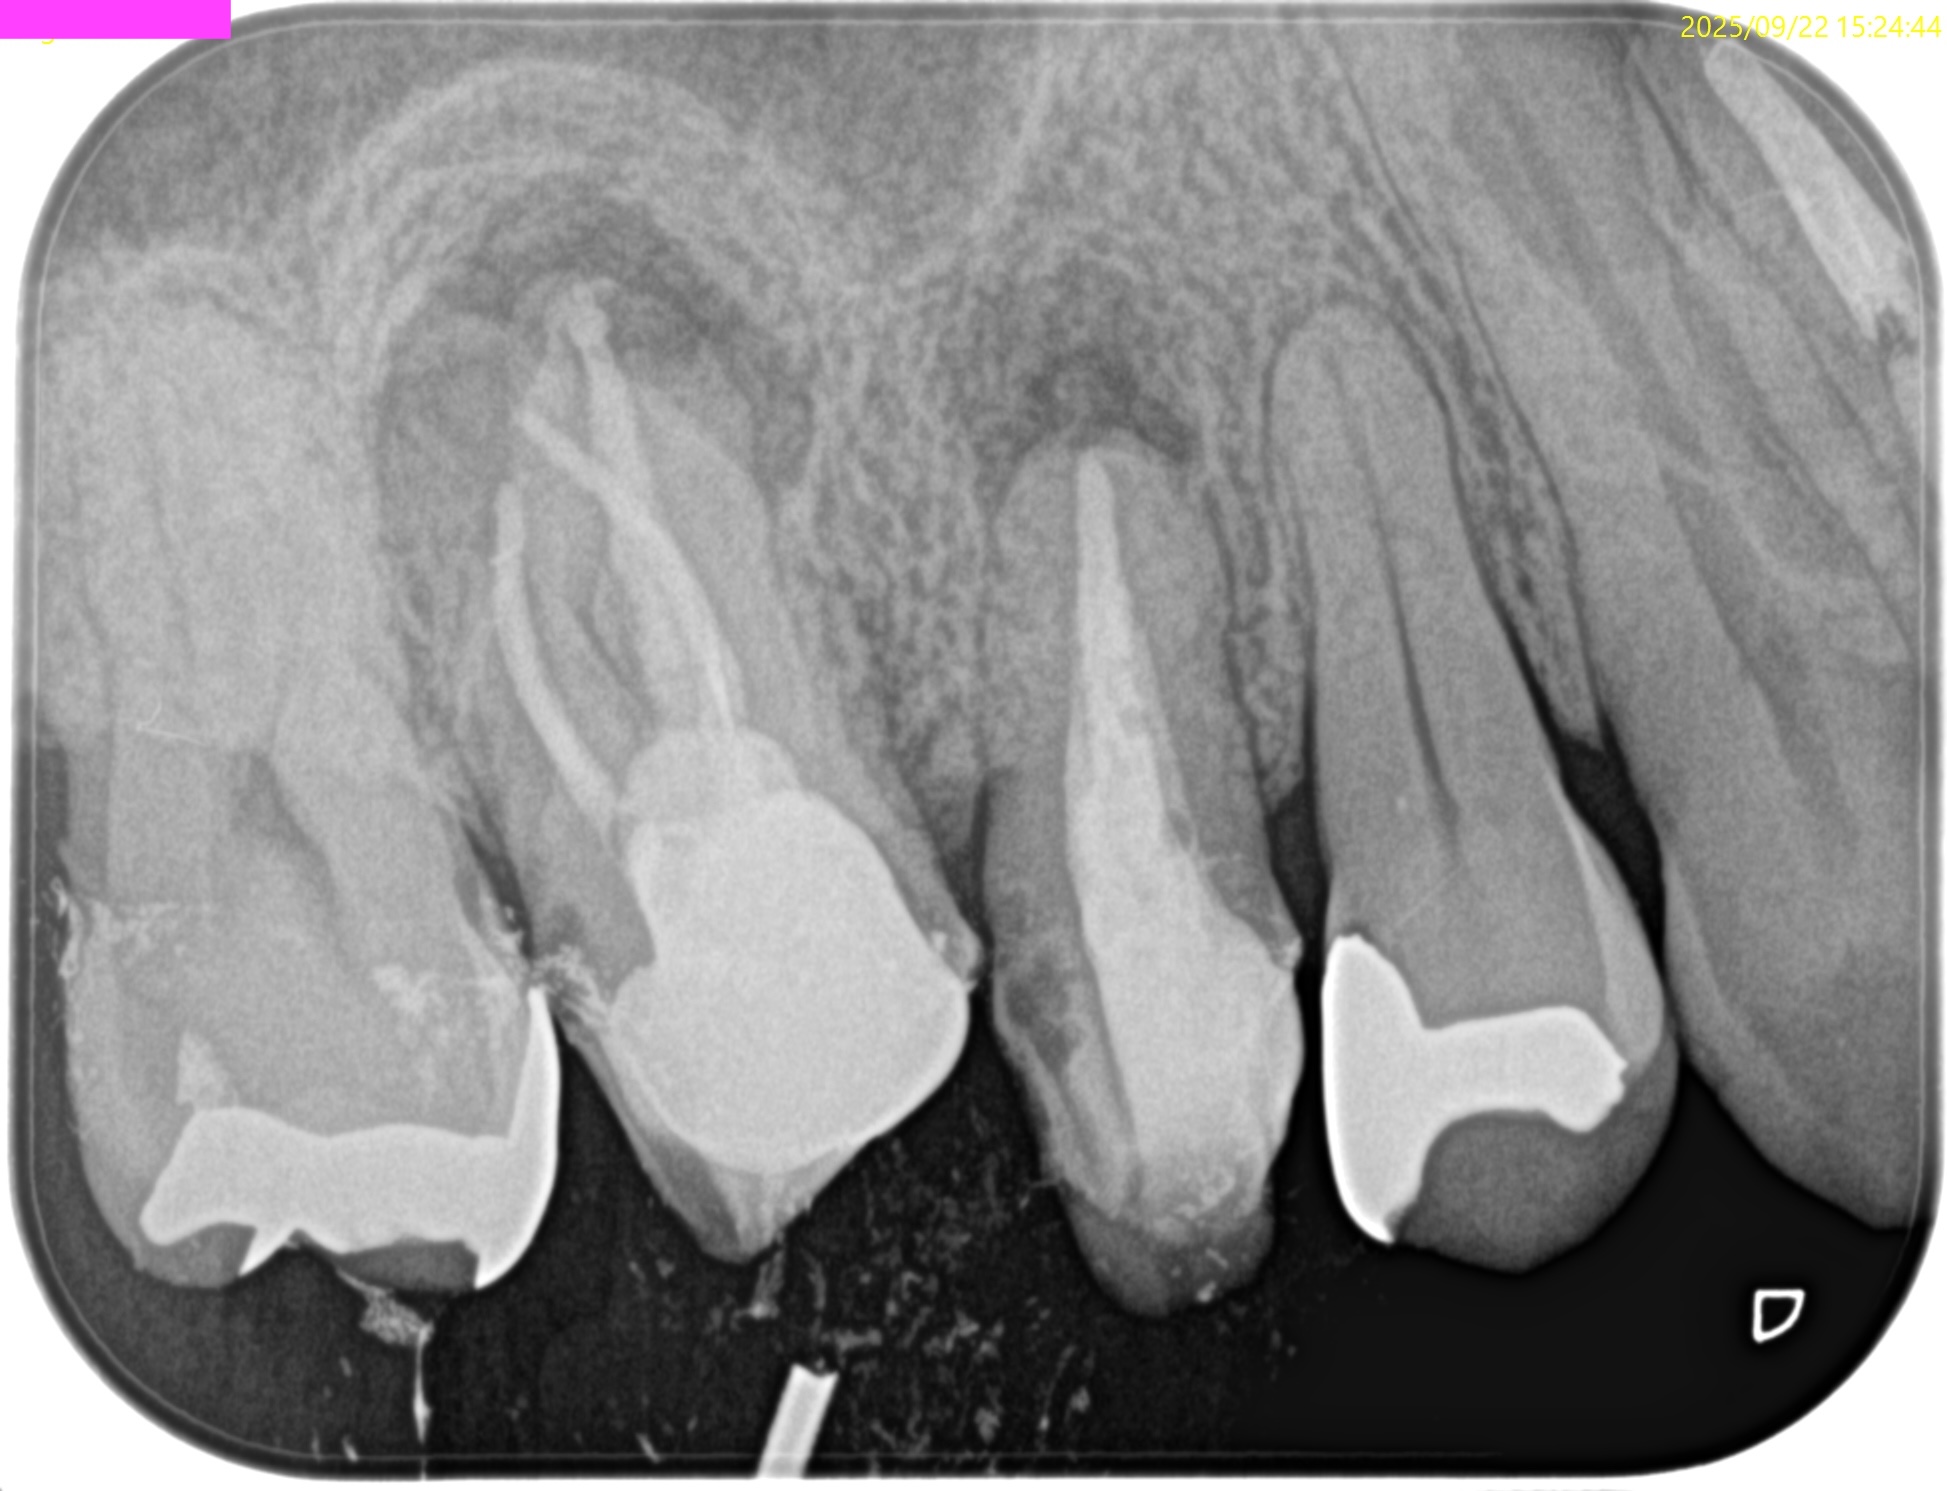

PA(2025.9.22)

これを治療した歯科医師は何もしていないに等しいだろう。

これで抜歯とは…

患者さんが疑念を持って正解だ。